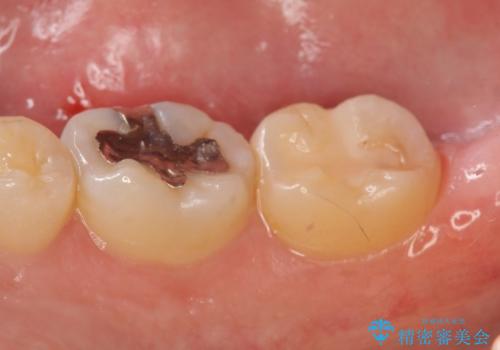

- 右下の一番奥の歯で冷たいものを飲むとしみるので診て欲しいといらっしゃった方の症例です。

ついでに銀歯もやり替えたいとのことだったので、右下6、7番目の歯に対してセラミックインレーによる修復を行いました。